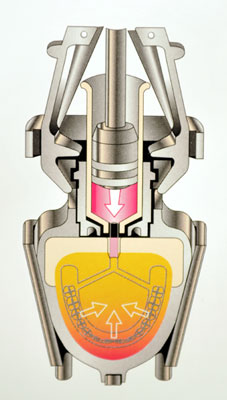

На сегодняшний день существует современная технология изготовления съемных протезов – системой литьевого прессования пластмассы IVOCAP-SYSTEM. Особенность этой системы состоит в том, пластмасса не полимеризуется методом варки, как это обычно делается, а прессуется под постоянным давлением и температурой. Это влияет на свойства протеза - увеличивает прочность, улучшает эстетический вид и уменьшает риск аллергических реакций. статья «Съемное протезирование» добавлена 2008-11-15 года